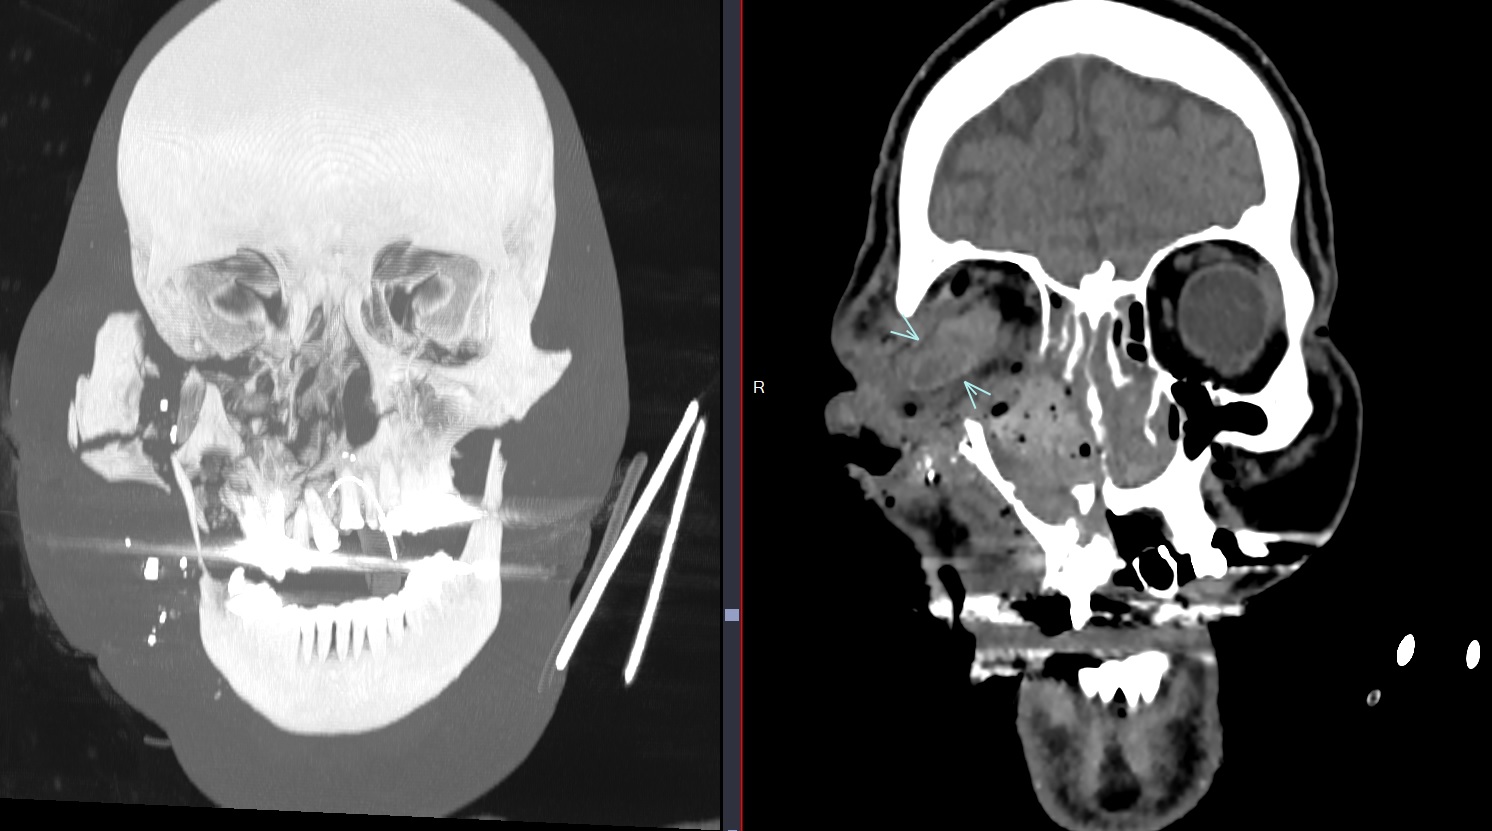

Cas

Sur Plaie par balle avec fracas facial